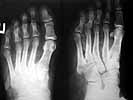

Diagnosis: a combined trauma of right autopodium (tarsus), extensive laceration and degloving, 2nd degree chemical burn up to 1 % of a body surface, closed fracture of navicular and clinoid (cuneiform?) bones.